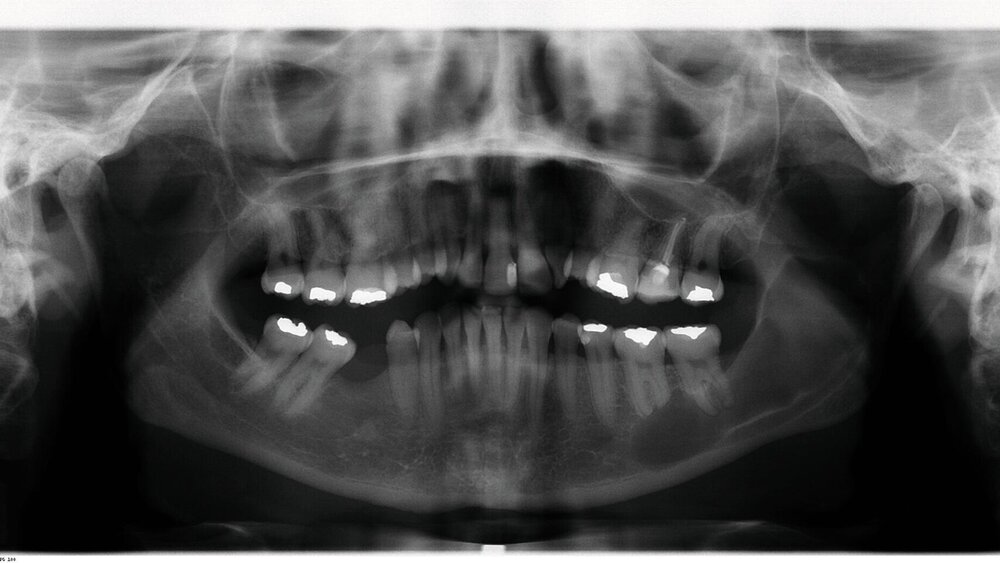

Im Rahmen der zahnärztlichen Routineuntersuchung fiel bei der seinerzeit 44-jährigen Frau eine zystische Läsion des linken aufsteigenden Unterkieferastes mit Ausdehnung nach mesial unter apikaler Beteiligung der Zähne 36 und 37 auf (Abbildung 1), woraufhin alio loco eine Zystektomie mit Wurzelspitzenresektion an den Zähnen 36 und 37 durchgeführt wurde.

Die histopathologische Beurteilung des enukleierten Zystenmaterials bestätigte die Verdachtsdiagnose einer Keratozyste. Als sich zwei Jahre später im Rahmen der regelmäßigen radiologischen Nachkontrollen erneut eine zystenähnliche Struktur im Bereich des linken aufsteigenden Unterkieferastes demarkierte, wurde die Patientin zur weiteren Diagnostik und Therapie an unsere Klinik überwiesen. Eine zusätzlich angefertigte digitale Volumentomografie (DVT) der betreffenden Region (Abbildung 2) erhärtete den klinischen Verdacht eines Keratozystenrezidivs, so dass zunächst eine erneute Zystektomie in Intubationsnarkose durchgeführt wurde.